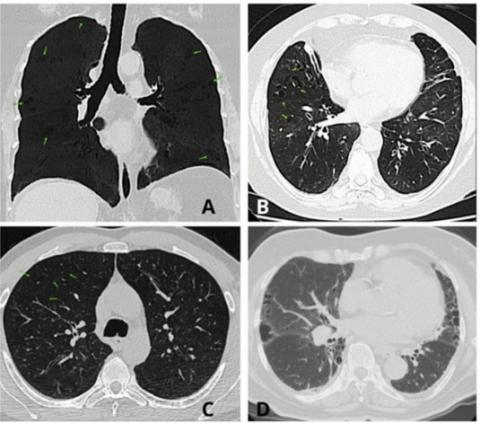

- El hallazgo de

enfisema en pacientes con vasculitis no fumadores se ha reportado en diversos

países.

- Existen patrones

repetitivos en las imágenes de los pulmones, como la presencia de pequeñas

zonas dañadas ubicadas en el centro o en los bordes del tejido pulmonar, que

permiten reconocer un tipo específico de enfisema relacionado con esta

enfermedad.